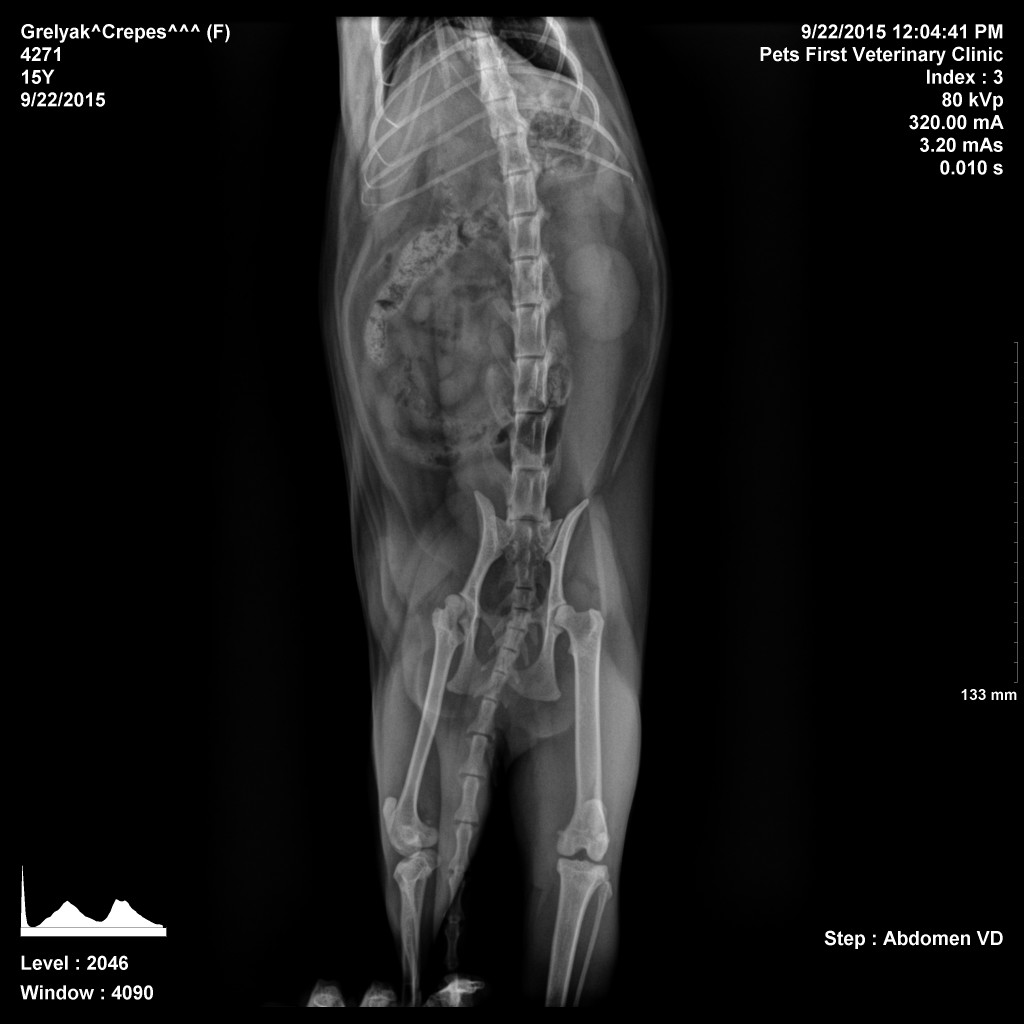

This is Crepes’ xray. Notice her hips – they are not only showing some curvature to one side, but the one on the left of this photo shows that her hip socket never properly formed, nor did the bone that fits into it. Essentially, her hip bone is never in the right place.

Additionally, if we look at her knee there, we can see that her kneecap is in the wrong place and is about an inch lower than is should be.

This all means that her injury is almost certainly congenital, meaning she was born this way. Unfortunately, it also means that she is probably suffering from quite a bit of discomfort. But what can we do about it?